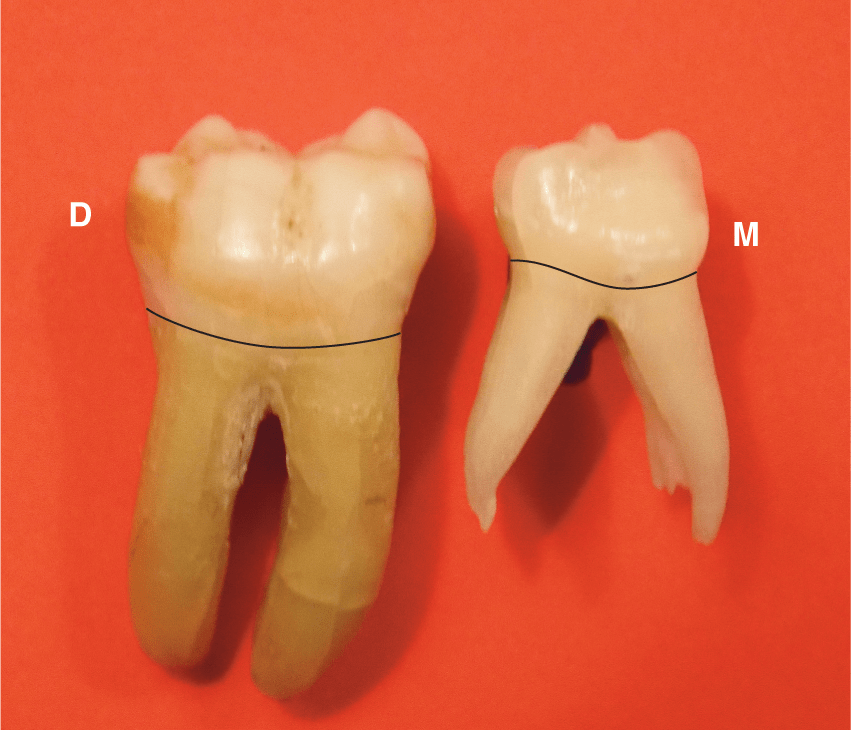

Molar

Maxillary

Mandibular